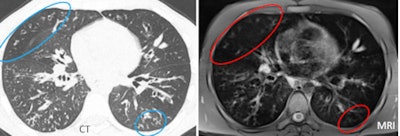

![]() |

| MRI tended to underestimate the severity of disease at the lung periphery. |